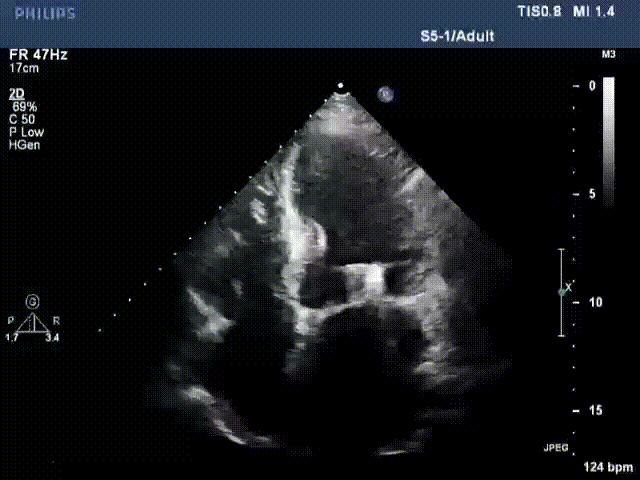

術(shù)前超聲提示二尖瓣重度反流

接受治療的是一例器質(zhì)性重度二尖瓣反流(DMR)患者,主訴“反復(fù)活動后胸悶,氣促3年余”。術(shù)前超聲顯示,雙房增大,二尖瓣脫垂伴重度反流,輕度三尖瓣反流,輕度肺高壓,升主動脈增寬。手術(shù)經(jīng)股靜脈-房間隔入路,采用全身麻醉插管,在TEE和DSA引導(dǎo)下完成房間隔穿刺。置入JensClip瓣膜夾系統(tǒng)后,在左房調(diào)整瓣膜夾的位置和軸向,后進(jìn)入左室,在TEE引導(dǎo)下捕捉二尖瓣前后瓣葉,并關(guān)閉瓣膜夾。經(jīng)TEE反復(fù)確認(rèn)手術(shù)效果后最終鎖定并釋放瓣膜夾。術(shù)后即刻超聲顯示瓣膜夾位置穩(wěn)定,功能良好,術(shù)前二尖瓣反流4+,術(shù)后0反流,肺靜脈逆流和左房壓都顯著好轉(zhuǎn),手術(shù)圓滿成功(以上數(shù)據(jù)都來源于醫(yī)院的臨床記錄)。術(shù)后患者狀態(tài)良好,目前已安排出院。